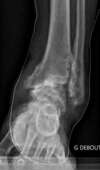

Arthrose de cheville post traumatique (séquelle d'entorses à répétition), traitée par blocage articulaire (arthrodèse)